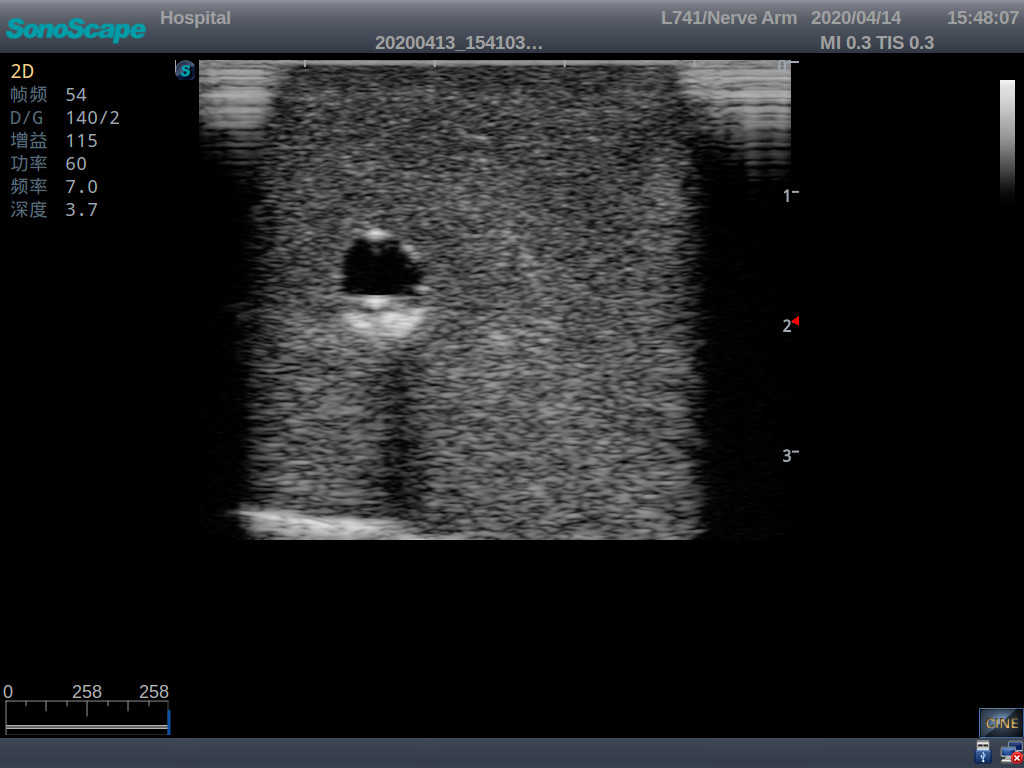

1)   Made of high molecular polymer ultrasound material, close to the real skin

2)   It can be used by real ultrasound machines

3)   Clear and real images of the tissues and organs (basilic vein and superior vena cava)

6)   Detect whether the catheter is properly placed